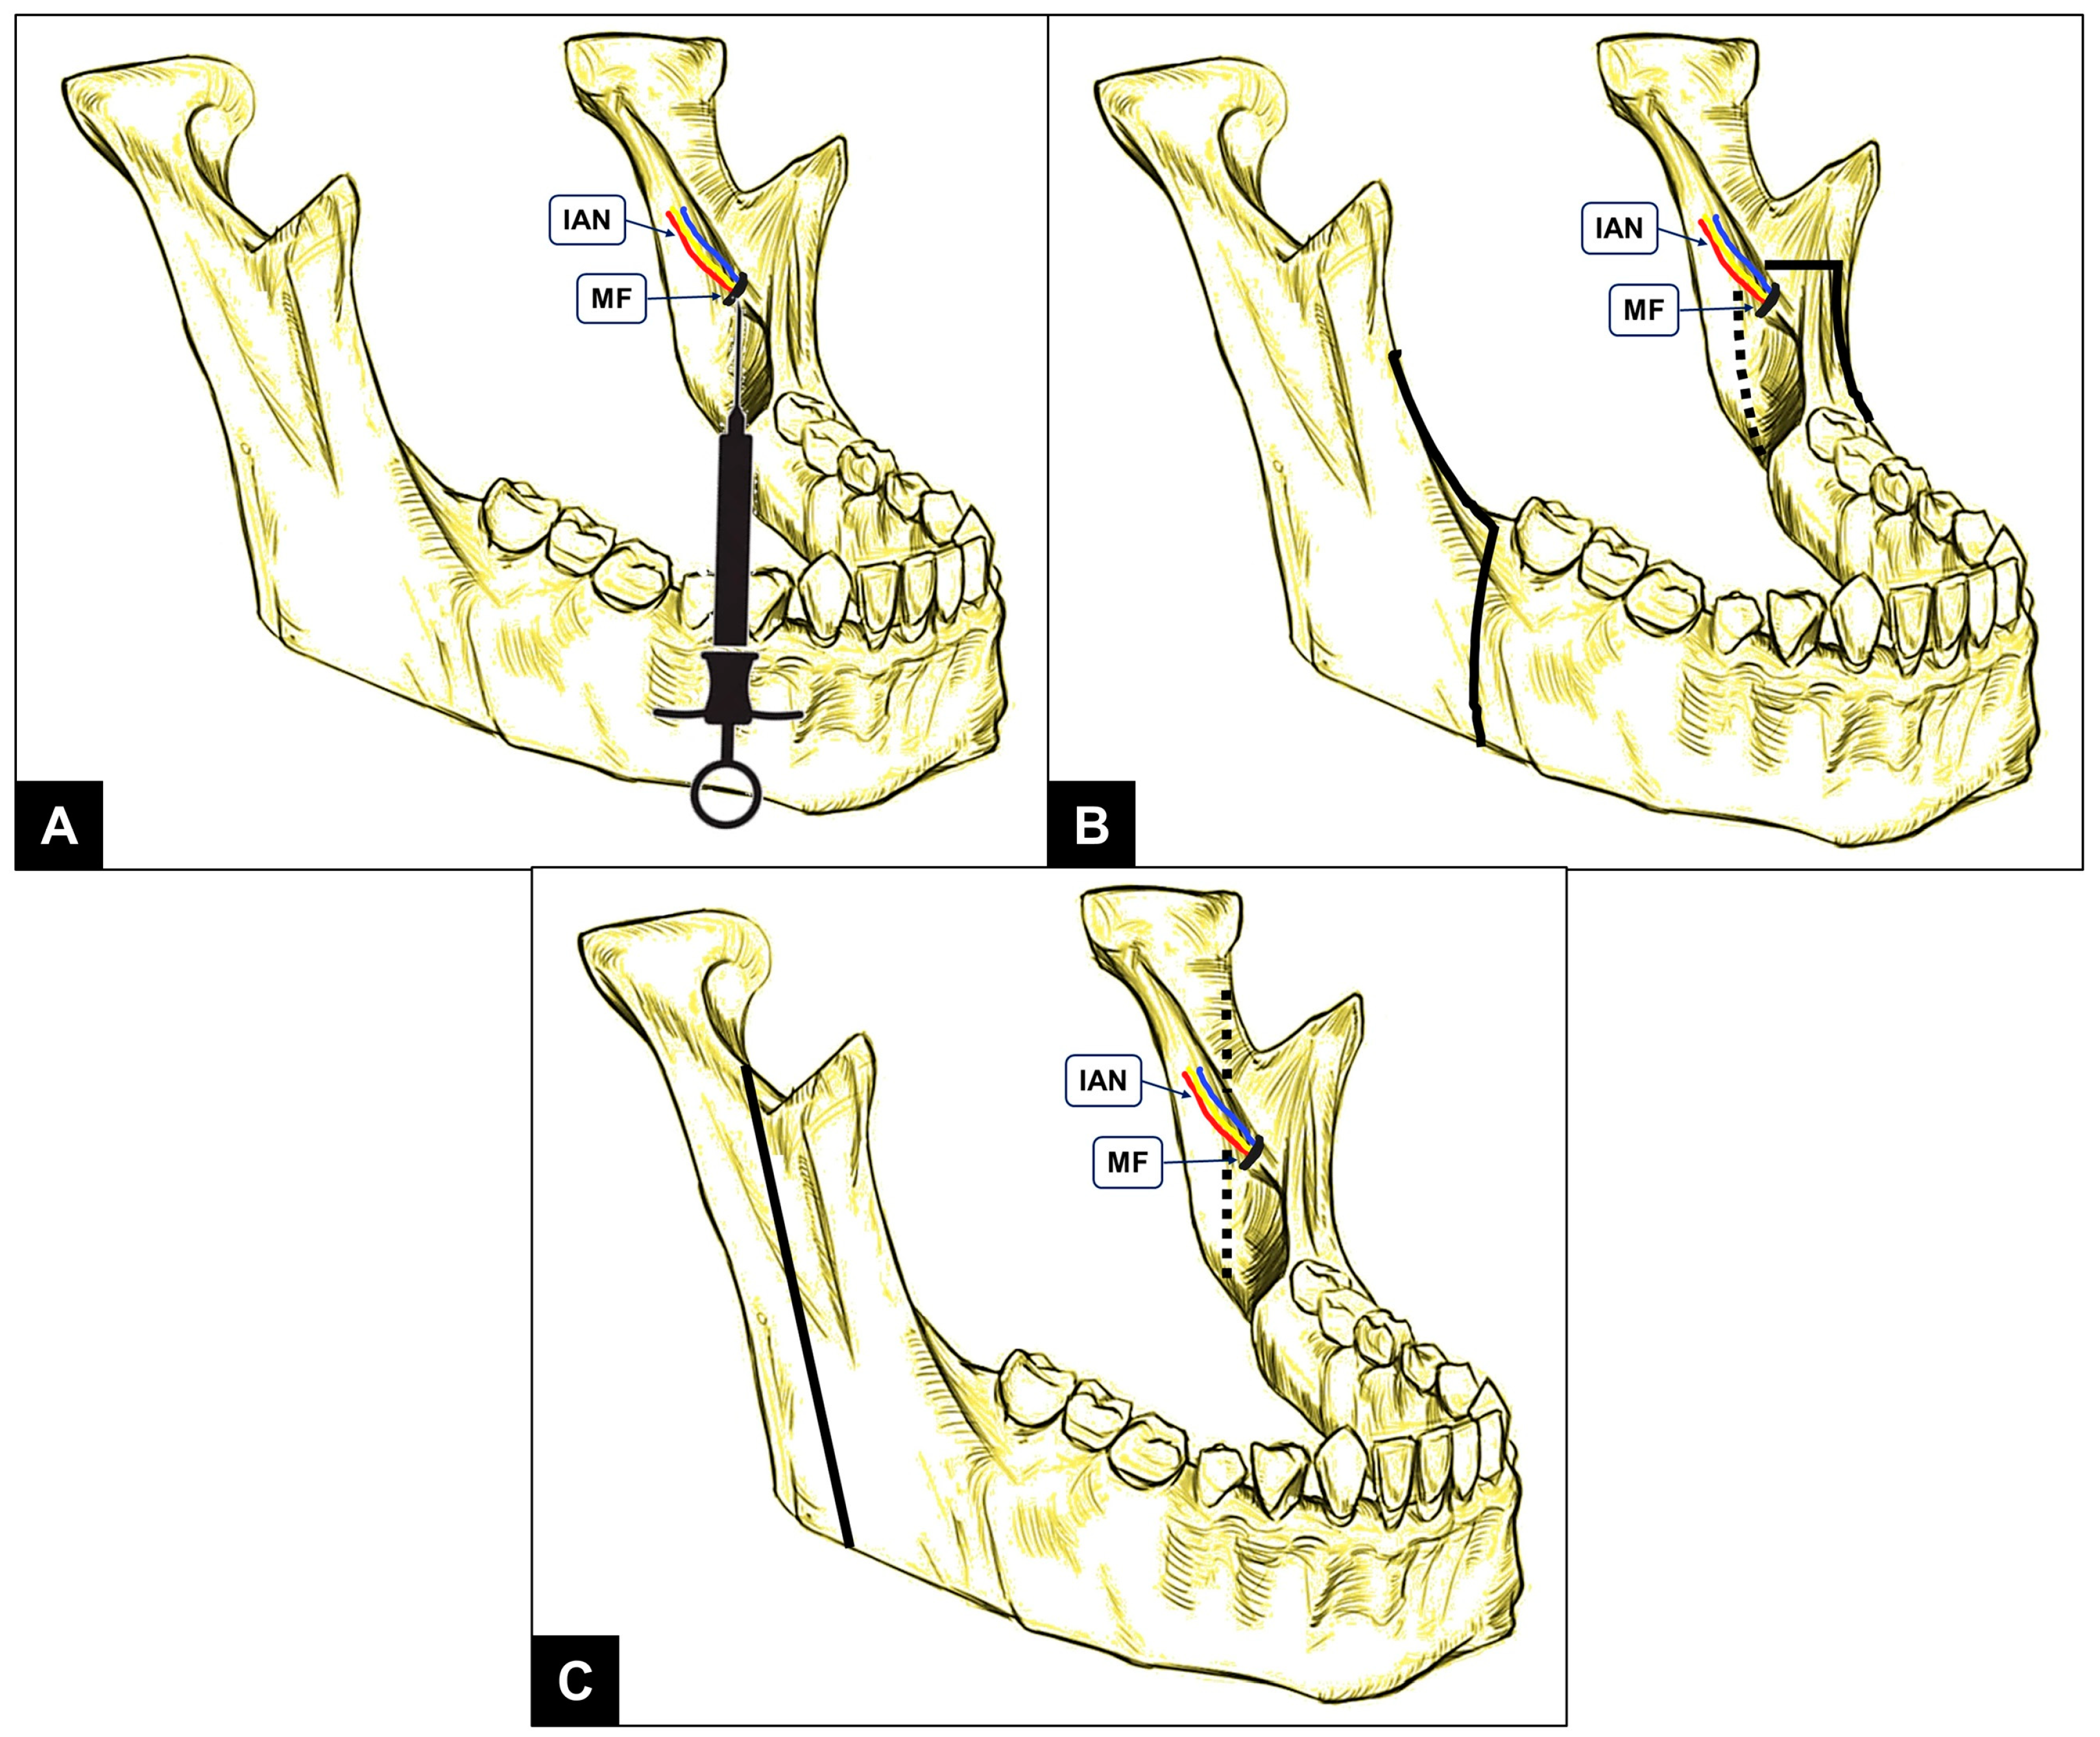

| Variable | Description | Radiographic Technique | Abbreviation Based on Anatomic Localization | |

|---|---|---|---|---|

| Right | Left | |||

| Anteroposterior position of mandibular foramen | Horizontal distance from anteroinferior border of mandibular foramen to anterior border of mandibular ramus | OPG | MF-AP-OPG (Right) | MF-AP-OPG (Left) |

| CBCT | MF-AP-CBCT (Right) | MF-AP-CBCT (Left) | ||

| Superoinferior position of mandibular foramen | Vertical distance from anteroinferior border of mandibular foramen to mandibular occlusal plane (at level of mesial cusp of first molar) | OPG | MF-SI-OPG (Right) | MF-SI-OPG (Left) |

| CBCT | MF-SI-CBCT (Right) | MF-SI-CBCT (Left) | ||